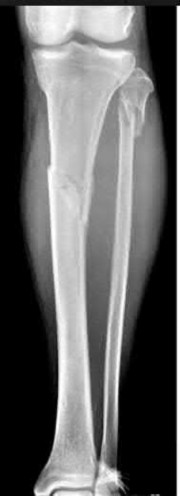

A 28-year-old male sustains a closed comminuted tibial shaft fracture.

Two hours post-injury, he develops severe leg pain unyielding to narcotics. His blood pressure is 120/80 mmHg. Intracompartmental pressure monitoring is performed. Based on current guidelines, which measurement dictates an emergent 4-compartment fasciotomy?